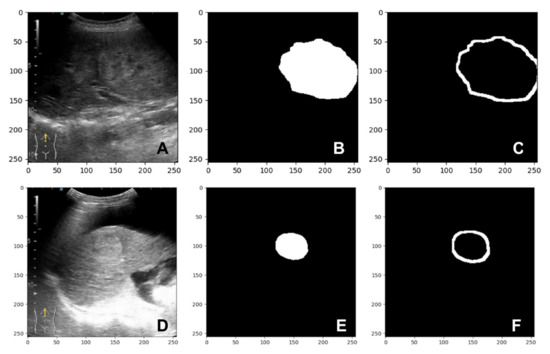

After applying dilation on the predicted mask, a new image was obtained: the dilated mask. By applying dilation to the predicted mask pixels, the boundaries of the lesion are increased. Since both images, the predicted mask and the dilated mask, are binary images, a difference between the dilated mask and the predicted mask can be calculated to obtain a mask which represented the parenchyma surrounding the lesion. Two samples are shown in Figure 4. We present the B-mode images of the lesions in Figure 4A,D. In Figure 4B,E the predicted masks by the segmentation model for 4A and 4D are presented, and 4C presents the mask for the parenchyma surrounding the lesions.

Figure 4. Sample frame from a patient with hepatocarcinoma: (A,D) B-mode frame; (B,E) predicted mask; (C,F) parenchyma mask.